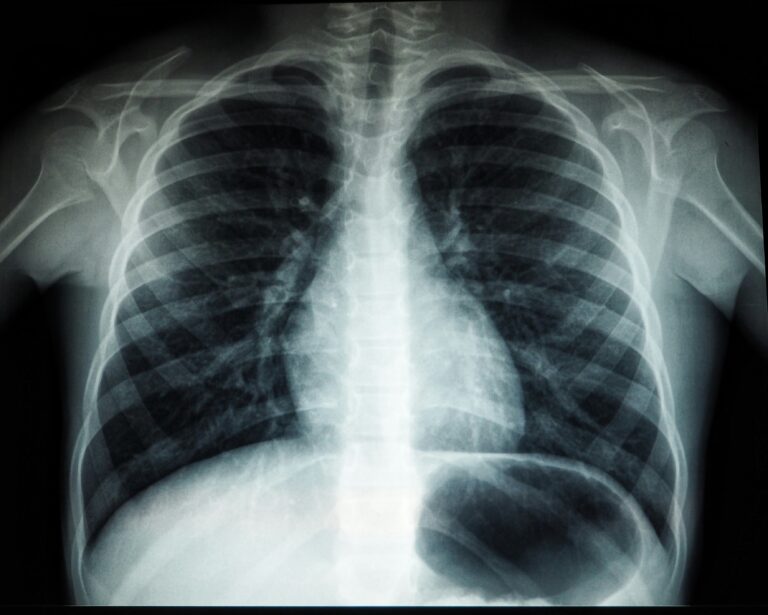

Tuberculosis, or TB, is an infection caused by bacteria that usually affects the lungs. It spreads when someone with active TB coughs, sneezes, or talks,

Tuberculosis (TB) is a serious infection that affects the lungs and sometimes other parts of the body. Treating TB requires taking a combination of medicines

Tuberculosis (TB) is a serious infection caused by bacteria called Mycobacterium tuberculosis. It usually affects the lungs but can also affect other parts of the